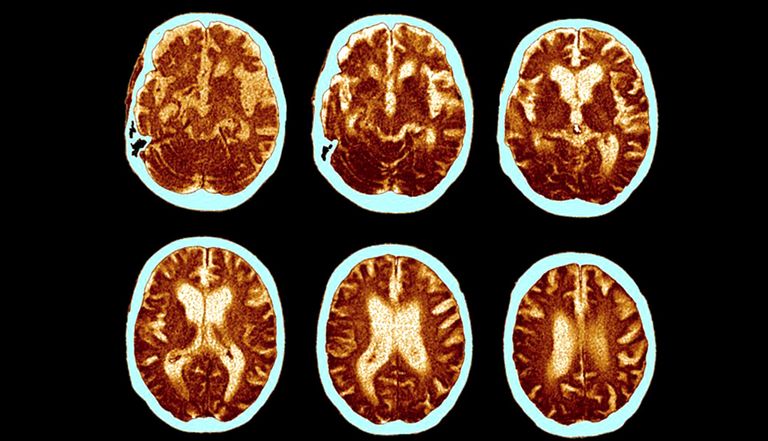

وأظهرت الأرقام الرسمية أن الخلل العقلي أو الزهايمر أحد الأسباب المؤدية إلى موت النساء أكثر من الرجال، لافتًا إلى أن الخلل العقلي يؤدي إلى الوفاة أكثر من سرطان الثدي.